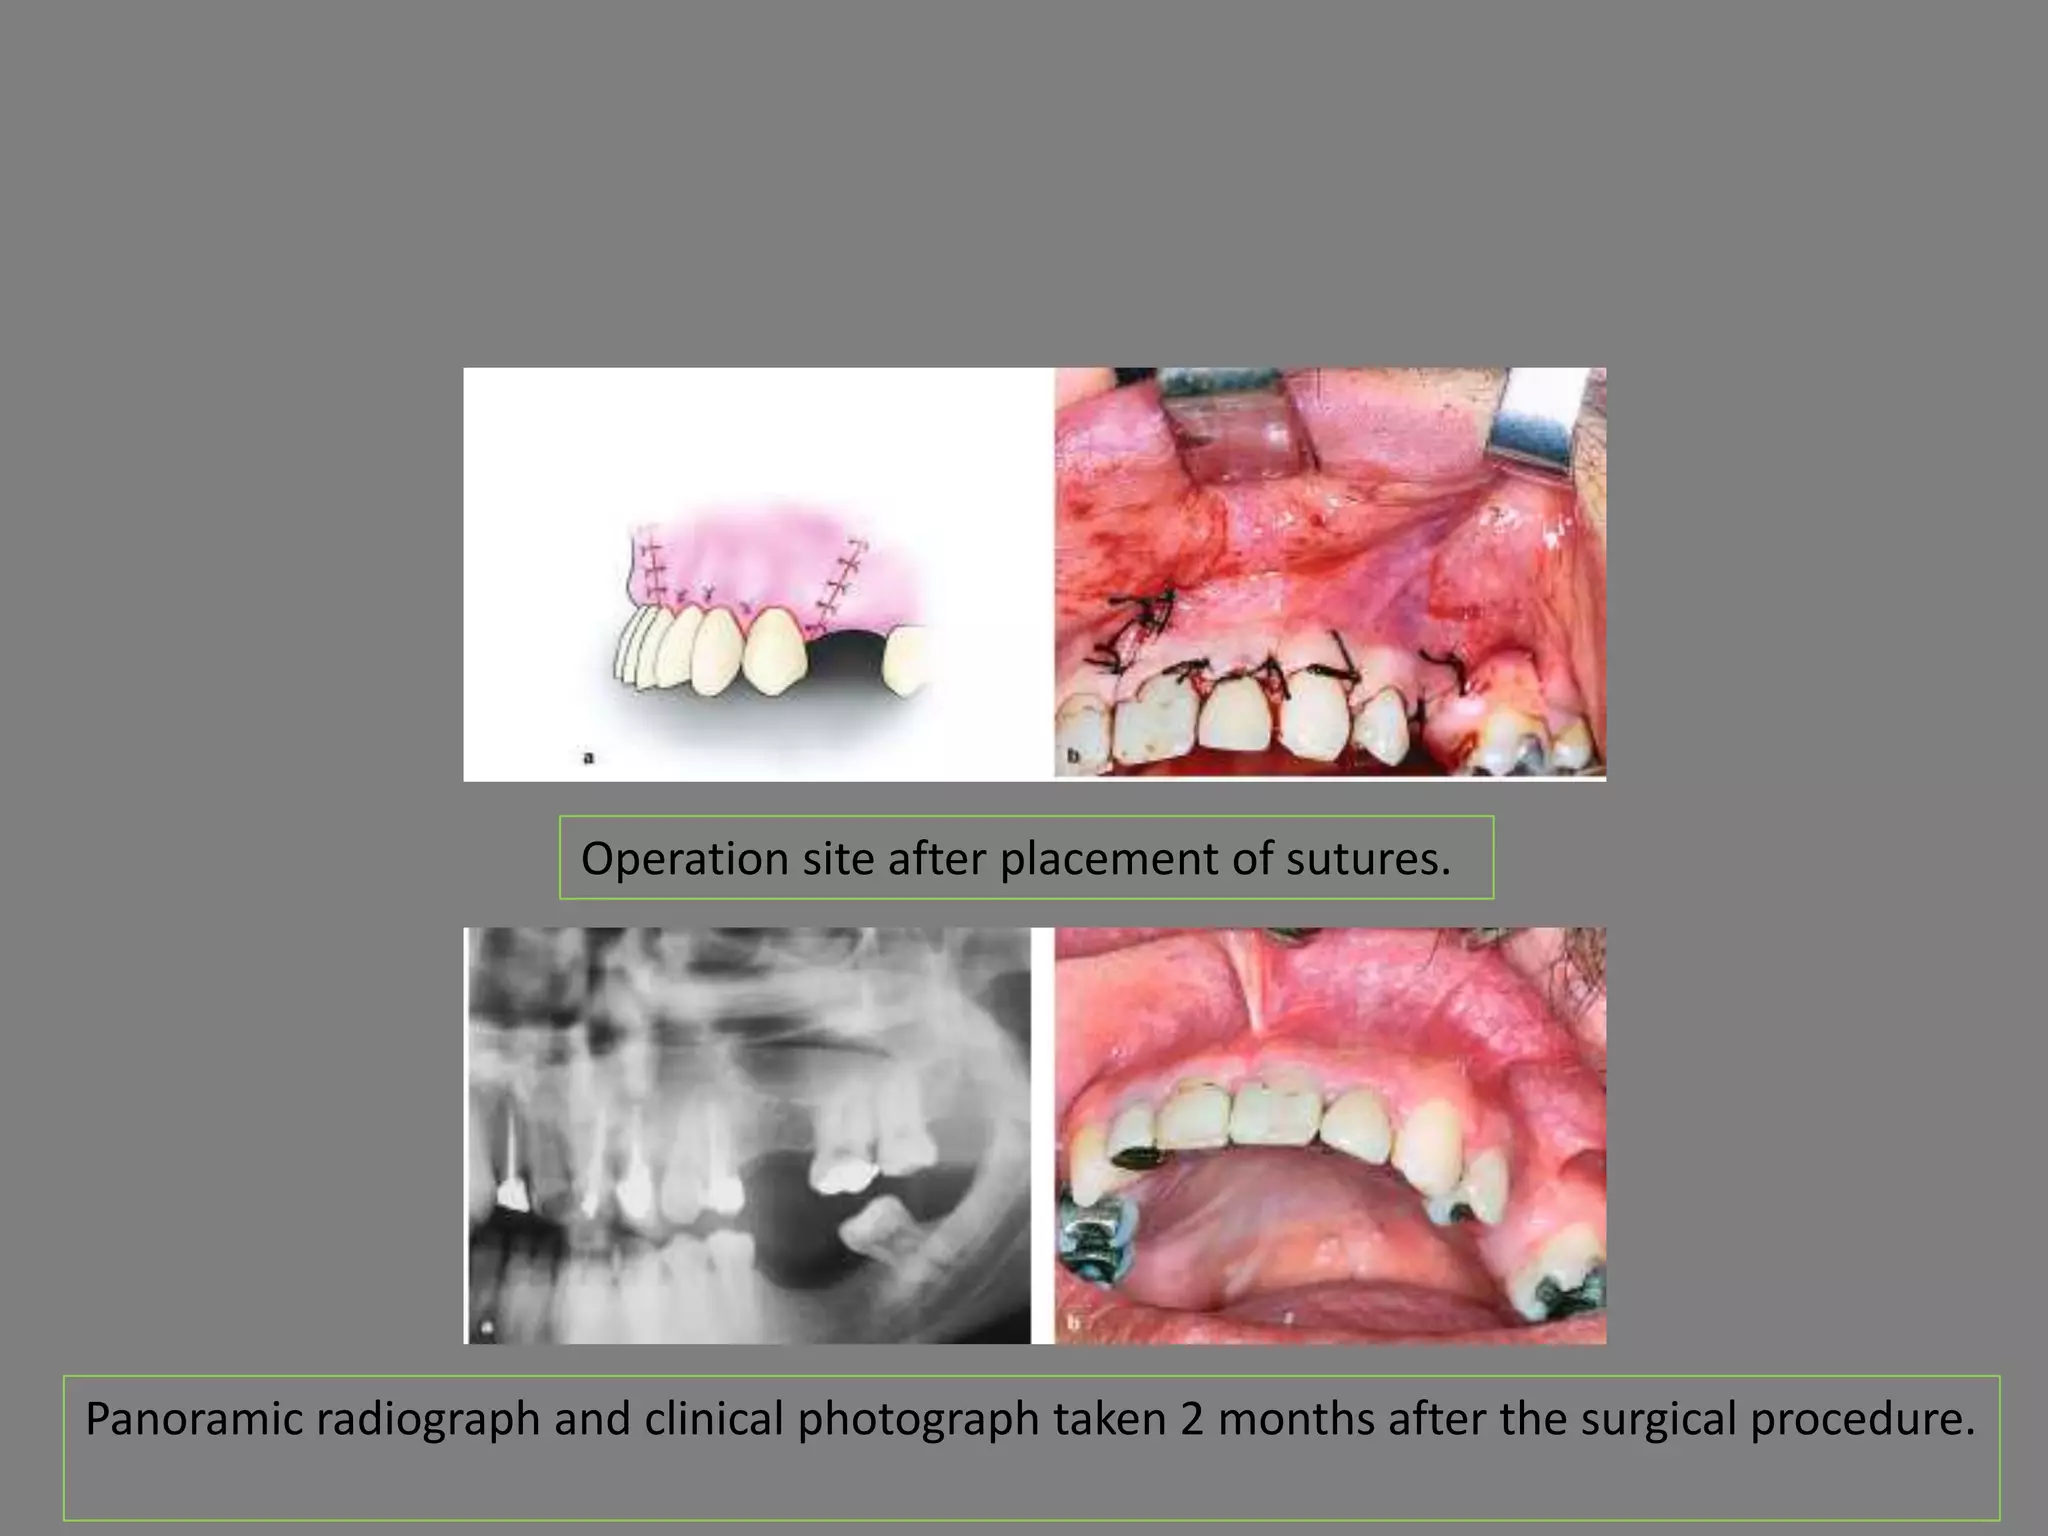

Operation site after placement of sutures.

Panoramic radiograph and clinical photograph taken 2 months after the surgical procedure.

Operation site afterplacement of sutures. Panoramic radiograph and clinical photograph taken 2 months after the surgical procedure.